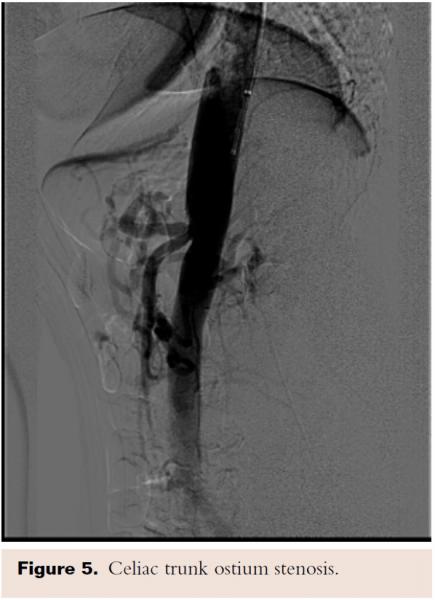

Given her age and co-morbid disease, the patient’s risk stratification was high for a moderate-to-high risk procedure; the patient was judged to be a poor surgical candidate and so the decision was made to refer her to interventional cardiology for consideration of less invasive treatment. A selective angiography of the celiac trunk was performed via the right common femoral artery with a 6 Fr system. During angiography, both inspiration and expiration films were compared; celiac artery stenosis was more prominent during expiration, and a characteristic superior indentation was noted along the proximal celiac axis (Figure 2), which led to the confirmation of MALS diagnosis. The celiac trunk was engaged with a 5 Fr, 0.035˝ Slip-cath VS 80 cm (Cook Medical), and the lesion was crossed with a 0.035˝ guidewire (Boston Scientific). Percutaneous transluminal angioplasty (PTA) of the proximal celiac trunk was performed with a 6.0 x 20 mm Mustang balloon (Boston Scientific). As expected, there was no significant angiographic improvement, so a 5.0 x 22 mm Cast stent (Atrium Medical Corporation) was deployed at 4 atm and postdilated at 10 atm. Final angiographic results showed reduced narrowing from 90% to 0%. IMA and SMA were patent (Figure 3).